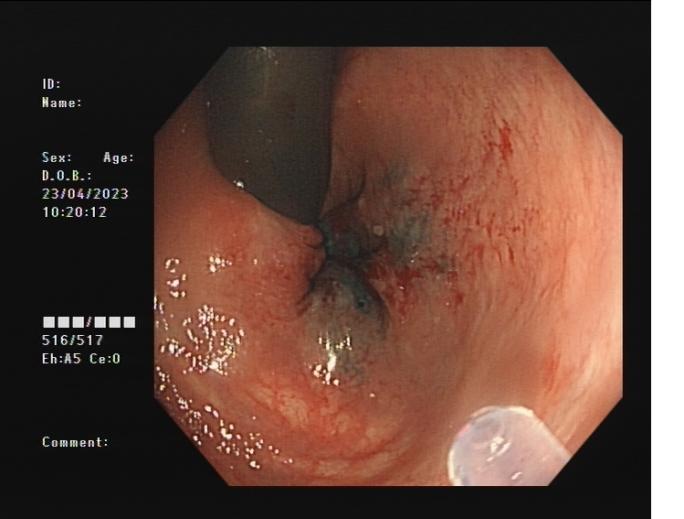

內痔 內鏡下內痔硬化治療

內鏡下內痔硬化術:治療I-Ⅲ度內痔伴有內痔相關癥狀;I~Ⅲ級內痔飲食及藥物治療無效;內痔手術后復發,肛門反復手術后不能再次手術;恐懼外科手術,不愿意接受手術治療;高齡、高血壓、糖尿病和嚴重的系統性疾病,不能耐受外科手術等。